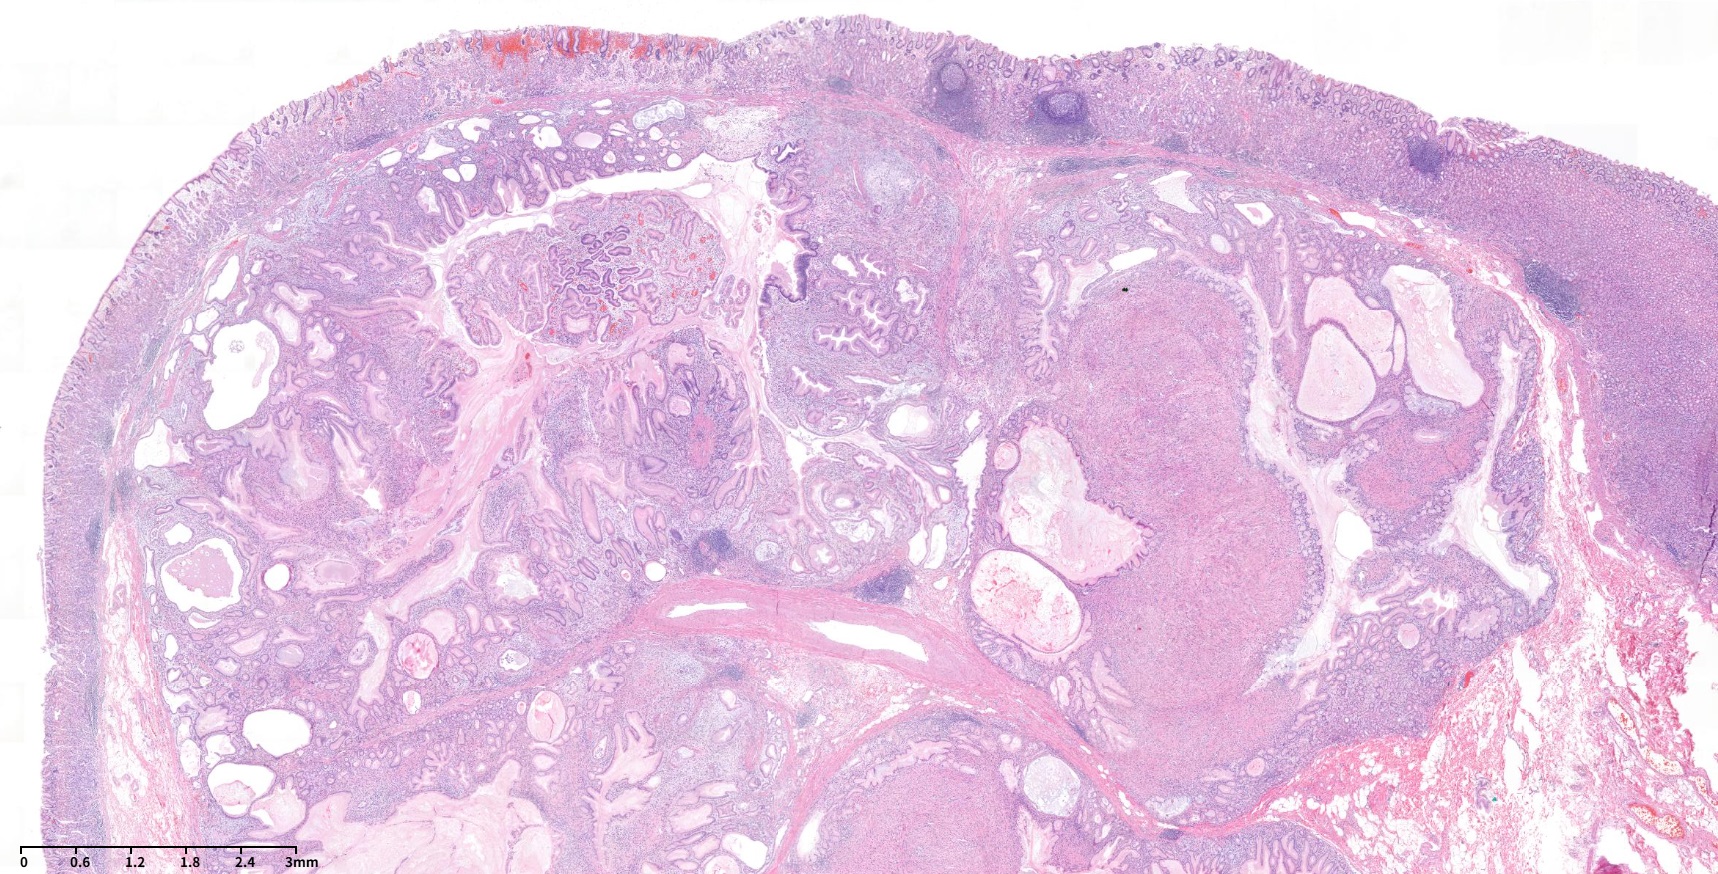

60¼¼ ³²¼ºÀÌ °Ç°­°ËÁø ³»½Ã°æ¿¡¼­ ¿ì¿¬È÷ ¹ß°ßµÈ À§ÀúºÎÀÇ 3cmÅ©±âÀÇ umbilicated ulcer¸¦ µ¿¹ÝÇÑ Á¡¸·ÇÏÁ¾¾ç ¼Ò°ßÀ¸·Î ÀǷڵǾú´Ù. ³»½Ã°æ °Ë»ç ´ç½Ã Á¶Á÷°Ë»ç ºÎÀ§ Áß ÇÑ °÷¿¡¼­ white thick mucinous materialÀÌ »ßÁ®³ª¿À´Â ¼Ò°ßÀÌ º¸¿´°í (»çÁø 1½Ã ¹æÇâ) ÂðµæÇÑ ´À³¦ÀÇ Á©¸®°°±âµµ ÇßÁö¸¸ Æ÷¼ÁÀ¸·Î ÀâÈ÷Áö´Â ¾Ê´Â´Ù´Â ¼Ò°ßÀÌ ±â¼úµÇ¾î ÀÖ¾ú´Ù. ¿ÜºÎ Á¶Á÷°Ë»ç °á°ú´Â stromal cell proliferation in lamina propria¿´°í ¾Ç¼º GIST (gastrointestinal stromal tumor) °¡´É¼ºÀÌ °í·ÁµÇ¾ú´Ù. ÀÇ·Ú ÈÄ ¿ÜºÎ ½½¶óÀ̵å ÀçÆÇµ¶ÇÑ ¼Ò°ßÀº Spindle cell tumor. differential diagnosis: GISTÀ̾ú´Ù. ³»½Ã°æ Àç°ËÀ» ÇÏ¿´°í À°¾È ¼Ò°ßÀº ºñ½ÁÇßÀ¸¸ç Á¶Á÷°Ë»ç Àç°ËÀº Chronic gastritis, active, with erosion, No definite submucosal tissue included·Î º¸°íµÇ¾úÀ¸¸ç DOG-1°ú C-KIT (CD 117)¿¡ ´ëÇÑ ¸é¿ªÇü±¤¿°»öÀº À½¼ºÀ̾ú´Ù. CT¸¦ ½ÃÇàÇÏ¿´À¸¸ç À§ÀúºÎ¿¡ ¾à 3 cmÀÇ endophytic mass°¡ ÀÖÀ¸¸ç central umbilicationÀÌ ÀÖ¾úÀ¸¸ç Á¤»ó mucosa·Î µ¤¿©ÀÖ¾î Á¡¸·ÇÏÁ¾¾çÀÇ °¡´É¼ºÀÌ ÀÖ´Â °ÍÀ¸·Î ÆÇµ¶µÇ¾ú´Ù. ºñ·Ï Á¶Á÷°Ë»ç¿¡¼­ È®ÀεÇÁö´Â ¾Ê¾ÒÀ¸³ª spindle cell proliferationÀÌ È®ÀÎµÈ ¹Ù ÀÖ°í ³»½Ã°æ À°¾È¼Ò°ß¿¡¼­ Áß¾ÓÀÇ Ç¥¸éÀÌ ºÒ±ÔÄ¢ÇÑ ÇÔ¸ôºÎ°¡ ÀÖ¾úÀ¸¹Ç·Î GISTÀÇ °¡´É¼ºÀ» °í·ÁÇÏ¿© ¿Ü°ú ÀÇ·ÚÇÏ¿© ½û±âÀýÁ¦¼úÀ» ÇÏ¿´´Ù. ÃÖÁ¾ º´¸® °á°ú´Â Herniated gastric mucosa with marked smooth muscle proliferation in submucosa, consistent with hamartomatous inverted polyp (1.7x1.6 cm)À̾úÀ¸¸ç desmin ¸é¿ªÇü±¤¿°»öÀº ¾ç¼ºÀ̾ú´Ù. À§ ¼Ó¸»¸² °ú¿ÀÁ¾¼º ¿ëÁ¾ (gastric inverted hamartomatous polyp, GIHP)Àº À§Á¡¸·ÇÏÃþ¿¡¼­ À§»ùÀÌ Áõ½ÄµÇ°í ³¶¼º È®ÀåÀ» º¸ÀÌ´Â °ÍÀ» Ư¡À¸·Î ÇÏ´Â ÁúȯÀÌ´Ù. º´¸®ÇÐÀûÀ¸·Î ÆòȰ±Ù Áõ½ÄÀ» º¸ÀÏ ¼ö ÀÖ´Ù. ÀϹÝÀûÀÎ °ú¿ÀÁ¾¼º ¿ëÁ¾ÀÌ ¿Ü¼ºÀå(exophytic growth)À» º¸ÀÌ´Â °Í¿¡ ºñÇÏ¿© GIHP´Â ³»¼ºÀå(endophytic growth)À» º¸ÀδÙ. ³»½Ã°æ ¼Ò°ß¿¡¼­ Ç¥¸éÀ¸·ÎºÎÅÍ ¿ìÀ¯°°Àº ¹Â½ÅÀÌ ¹èÃâµÉ ¼ö ÀÖ´Ù. ÃÊÀ½ÆÄ ³»½Ã°æ ¼Ò°ßÀº À̼Ҽº ÃéÀå Á¶Á÷°ú ±¸ºÐÀÌ ¾î·Æ´Ù. ¾à 20%ÀÇ ¾Ç¼ºÈ­ °¡´É¼ºÀÌ ÀÖÀ¸¹Ç·Î 2cm À̻󿡼­´Â ÀýÁ¦¼úÀ» ±ÇÇÑ´Ù.

Stomach, wedge resection: Herniated gastric mucosa with marked smooth muscle proliferation in submucosa, consistent with hamartomatous inverted polyp (1.7x1.6 cm)

GIHPs are a distinct entity characterized by submucosal growth of hypertrophic glands with cystic dilatation. They are distinct from the other types of hamartomatous polyps, which have an exophytic configuration contrary to the endophytic nature of these polyps. On endoscopic examination, these are reported as solitary submucosal masses. On endoscopy, extrusion of milky mucinous material from the surface of the lesion and calcifications from the biopsy site may provide a clue to diagnosis. On histology, there is cystic proliferation of glands, which may be accompanied by smooth muscle proliferation, and formation of ectopic duct-like structures has also been reported. In addition, fibroblastic and neural proliferation may also be seen with glandular elements. Diagnosis of GIHP is difficult without pathologic examination and may mimic ectopic pancreas on endoscopy and endosonography. Certain features have been suggested on endoscopic ultrasound imaging, such as hyperechoic lesions with hypoechoic spots, which might be suggestive of GIHPs. En bloc removal is recommended in lesions >2 cm due to the associated malignant risk (up to 20% risk of malignancy). Though it is rare, Hirasaki et al have reported a case of GHIP associated with signet ring cell carcinoma.

Wedge resection: herniated gastric mucosa in the submucosa with cystic dilatation

Herniated gastric mucosa in the submucosa